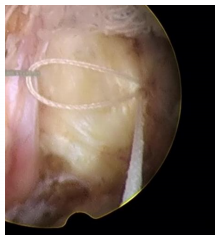

一次性使用纖維環(huán)縫合器技術(shù)特點(diǎn):

脊柱修復(fù)與重建技術(shù)之纖維環(huán)縫合術(shù)是在各種針對(duì)椎間盤突出癥的手術(shù)術(shù)式輔助下,閉合纖維環(huán)上殘留的破口,技術(shù)特點(diǎn)如下:

1、纖維環(huán)縫合手術(shù)是對(duì)椎間盤形態(tài)進(jìn)行的修復(fù),促進(jìn)了纖維環(huán)破口的愈合,是對(duì)以纖維環(huán)破裂所造成的椎間盤突出癥直接和有效的治療手段。

2、即刻閉合纖維環(huán)的破口,顯著降低椎間盤內(nèi)殘留髓核受力后從纖維環(huán)破口處再突出的復(fù)發(fā)幾率。

纖維環(huán)縫合技術(shù)是脊柱修復(fù)與重建領(lǐng)域一項(xiàng)基礎(chǔ)技術(shù),通過對(duì)突出椎間盤髓核摘除后纖維環(huán)上的破口進(jìn)行閉合處理,完成對(duì)椎間盤完整形態(tài)的修復(fù),降低椎間盤內(nèi)殘留髓核再突出的幾率,促進(jìn)纖維環(huán)愈合,對(duì)椎間盤功能的恢復(fù)具有積極影響;同時(shí),閉合的纖維環(huán)破口能夠減少盤內(nèi)炎性介質(zhì)的釋放,為重建神經(jīng)組織自然環(huán)境創(chuàng)造有利條件,從而提高患者術(shù)后生活質(zhì)量。該技術(shù)為手術(shù)治療腰椎間盤突出癥創(chuàng)造了一套更加完善的解決方案,更好的服務(wù)于患者。

適用于椎間孔鏡、椎間盤鏡、雙通道脊柱微創(chuàng)手術(shù)技術(shù)(UBE),顯微鏡、通道管等微創(chuàng)手術(shù)髓核摘除后纖維環(huán)的修復(fù),降低術(shù)后復(fù)發(fā)率